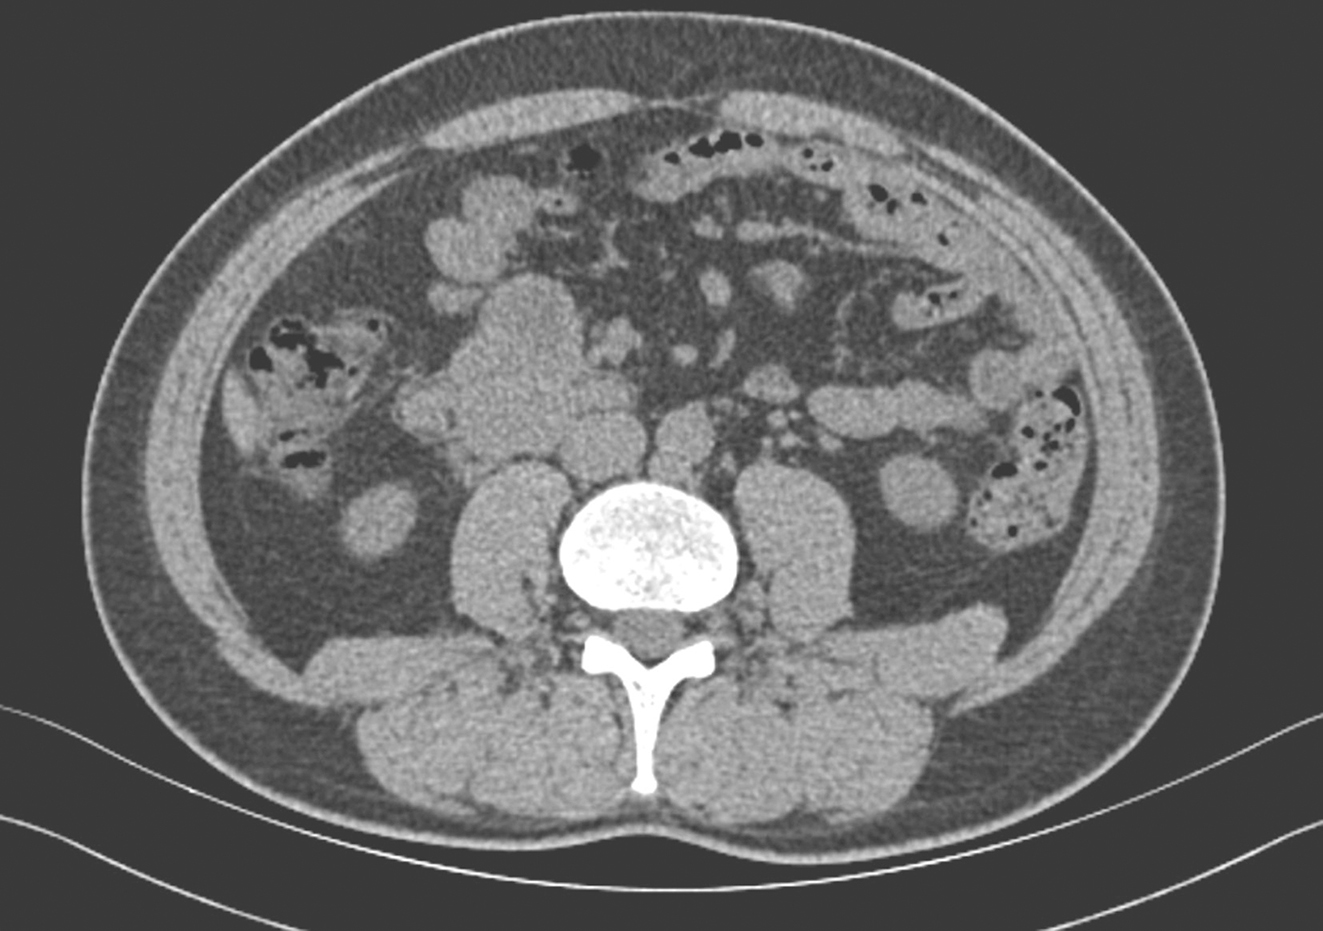

服药7个月后,2018年6月复查全腹增强CT示:十二指肠降部见等密度肿块影并向外生长,大小约6.1cm×4.4cm,病灶边界尚清,与胰腺钩突。下腔静脉毗邻;中央见不规则液体密度影,肝固有动脉分支向病灶供血,邻近肠系膜根部多发小淋巴结,增强示边缘实性成分可见强化,中心区域低密度影区未见明显强化;上述所见考虑十二指肠GIST,病灶较前略缩小。余与前片相仿,无特殊(图3)。

图3 2018年6月全腹增强CT